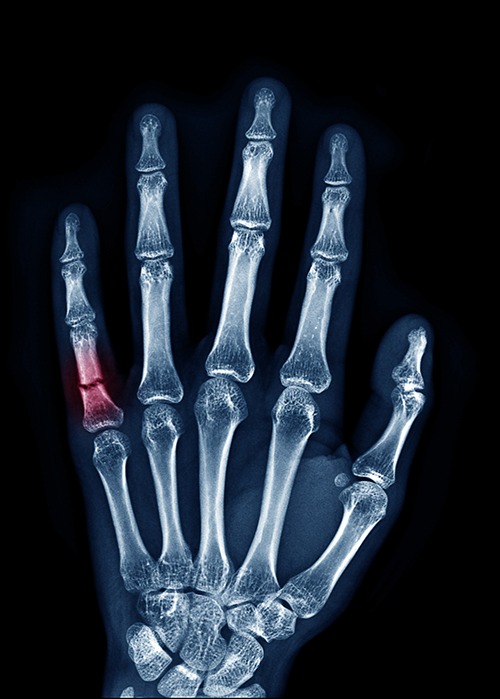

Finger fractures, involving the phalanx or metacarpal bones, can significantly affect hand function and overall quality of life. In cases where the fracture is displaced or unstable, surgical intervention may be necessary to restore proper alignment and promote optimal healing.

Finger fracture surgery involves repositioning the broken bones and securing them with screws, plates, or wires. This procedure aims to realign the bones accurately, enabling the fingers to regain their normal shape and function. Following the procedure, patients are often advised to undergo rehabilitation therapy to restore hand strength and range of motion.

Therefore, it is crucial to consult with a qualified orthopedic surgeon, who can assess the severity of the fracture and determine the most appropriate treatment option. Prompt surgical intervention for finger fractures can lead to a faster recovery and improved hand functionality, allowing patients to regain their normal activities in the shortest possible time.